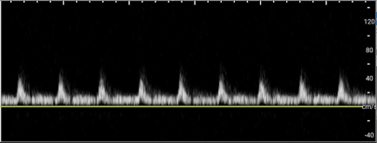

• A healthy testicle should appear oval-shaped and roughly 3–5 cm in length, by 2–3 cm in width depending on the age. Testicles have a homogeneous appearance with a medium-level echogenicity (like other solid organs). They are smooth and uniform throughout when healthy. Start by fanning through the testicle in transverse and longitudinal orientations to get a general assessment. When applying color Doppler to a well perfused testicle, there should be uniform, low velocity arterial and venous blood flow throughout the parenchyma. Vessels may appear pinpoint, linear or branching. Using spectral Doppler, the velocity of specific vessels can be measured. Arterial flow will appear as a brisk upstroke and sharp downstroke reflecting the cardiac cycle. Venous flow has a continuous velocity with less variation, often described as a “venous hum” (Images 6 and 7).7